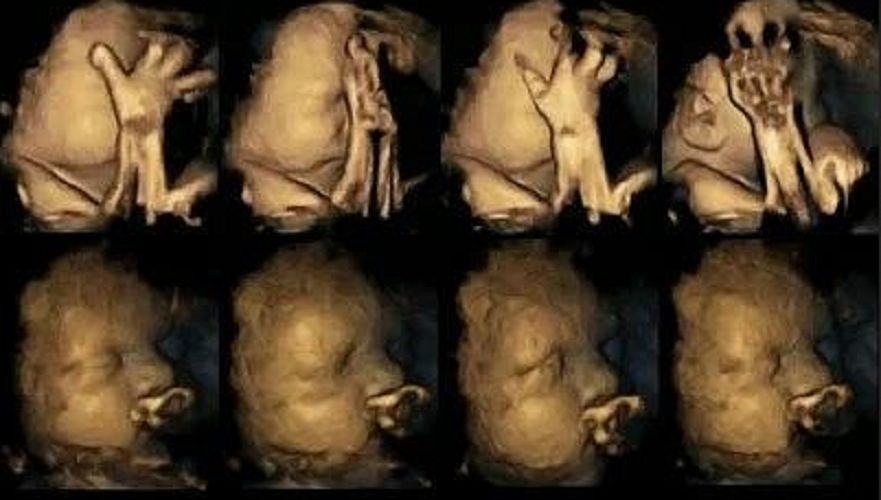

Zdjęcia USG dzieci, których matki paliły.Zdjęcia USG dzieci, których matki paliły

Źródło zdjęć: © Durham University

W kilku badaniach wykorzystano ultrasonografię 4D. Naukowcy obserwowali zachowania 8 dziewczynek oraz 7 chłopców. Dzięki temu wiadomo, że płód bardzo szybko zaczyna robić miny i gesty, które wyrażają jego uczucia czy emocje.

Badania wykazały, że mimika twarzy staje się bogatsza wraz z rozwojem dziecka. Zdaniem Nadji Reissland, autorki badań, w ten sposób dzieci ćwiczą jeszcze przed przyjściem na świat, aby później móc komunikować swój dyskomfort dorosłym. Reissland uważa także, że bogata mimika dziecka może świadczyć o prawidłowym rozwoju.

Naukowcy przeanalizowali mimikę tych dzieci, których matki paliły w ciąży. Płody były niespokojne. Znacznie częściej się ruszały i wykonywały dodatkowe gesty. To wskazuje, że nikotyna lub inne toksyny z dymu mają duży wpływ na rozwój płodu.

Płody częściej ruszały rękami i ustami. Ich aktywność nie malała wraz z postępem ciąży. U prawidłowo rozwijających się płodów taka aktywność spada z upływem czasu. To sugeruje, że płody mogą mieć opóźniony rozwój w ośrodkowym układzie nerwowym.

Na górze pokazany jest płód matki palącej a niżej matki niepalącej.